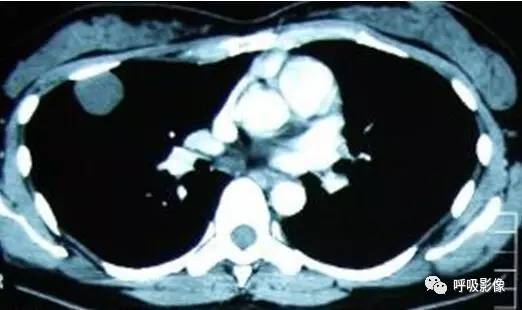

胸部CT示双肺多发结节影,强化明显,内见明显坏死,提示血供丰富。

转移瘤多具有原发肿瘤特点,本例转移瘤为生殖源性肿瘤,盆腔附件包块穿刺活检细胞学检病理均查见恶性肿瘤细胞,结合转移灶坏死、强化明显,需考虑绒毛膜癌可能。

胸部CT双肺多发结节影,强化明显,内见明显坏死,提示血供丰富,这是诊断关键。